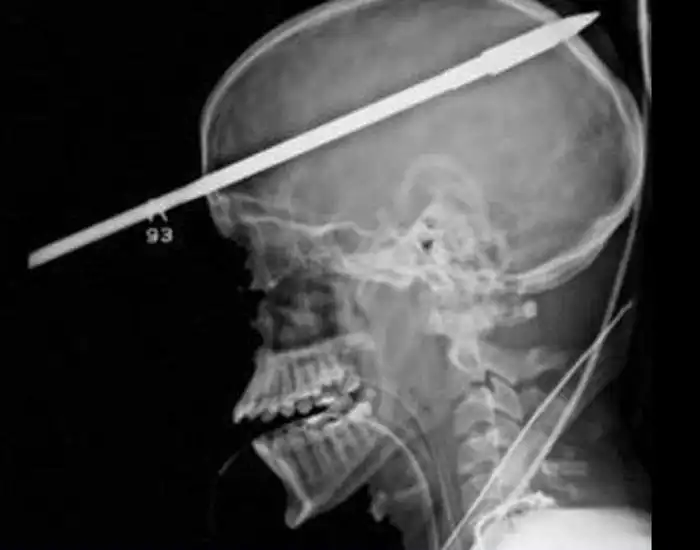

Необычные предметы в теле людей на рентгеновских снимках

На рентгеновских снимках людей порой можно обнаружить самые необычные предметы, которые находятся в их теле.

Человечество явно с гвоздями не дружит!!! Что не снимок то гвоздь в башке!